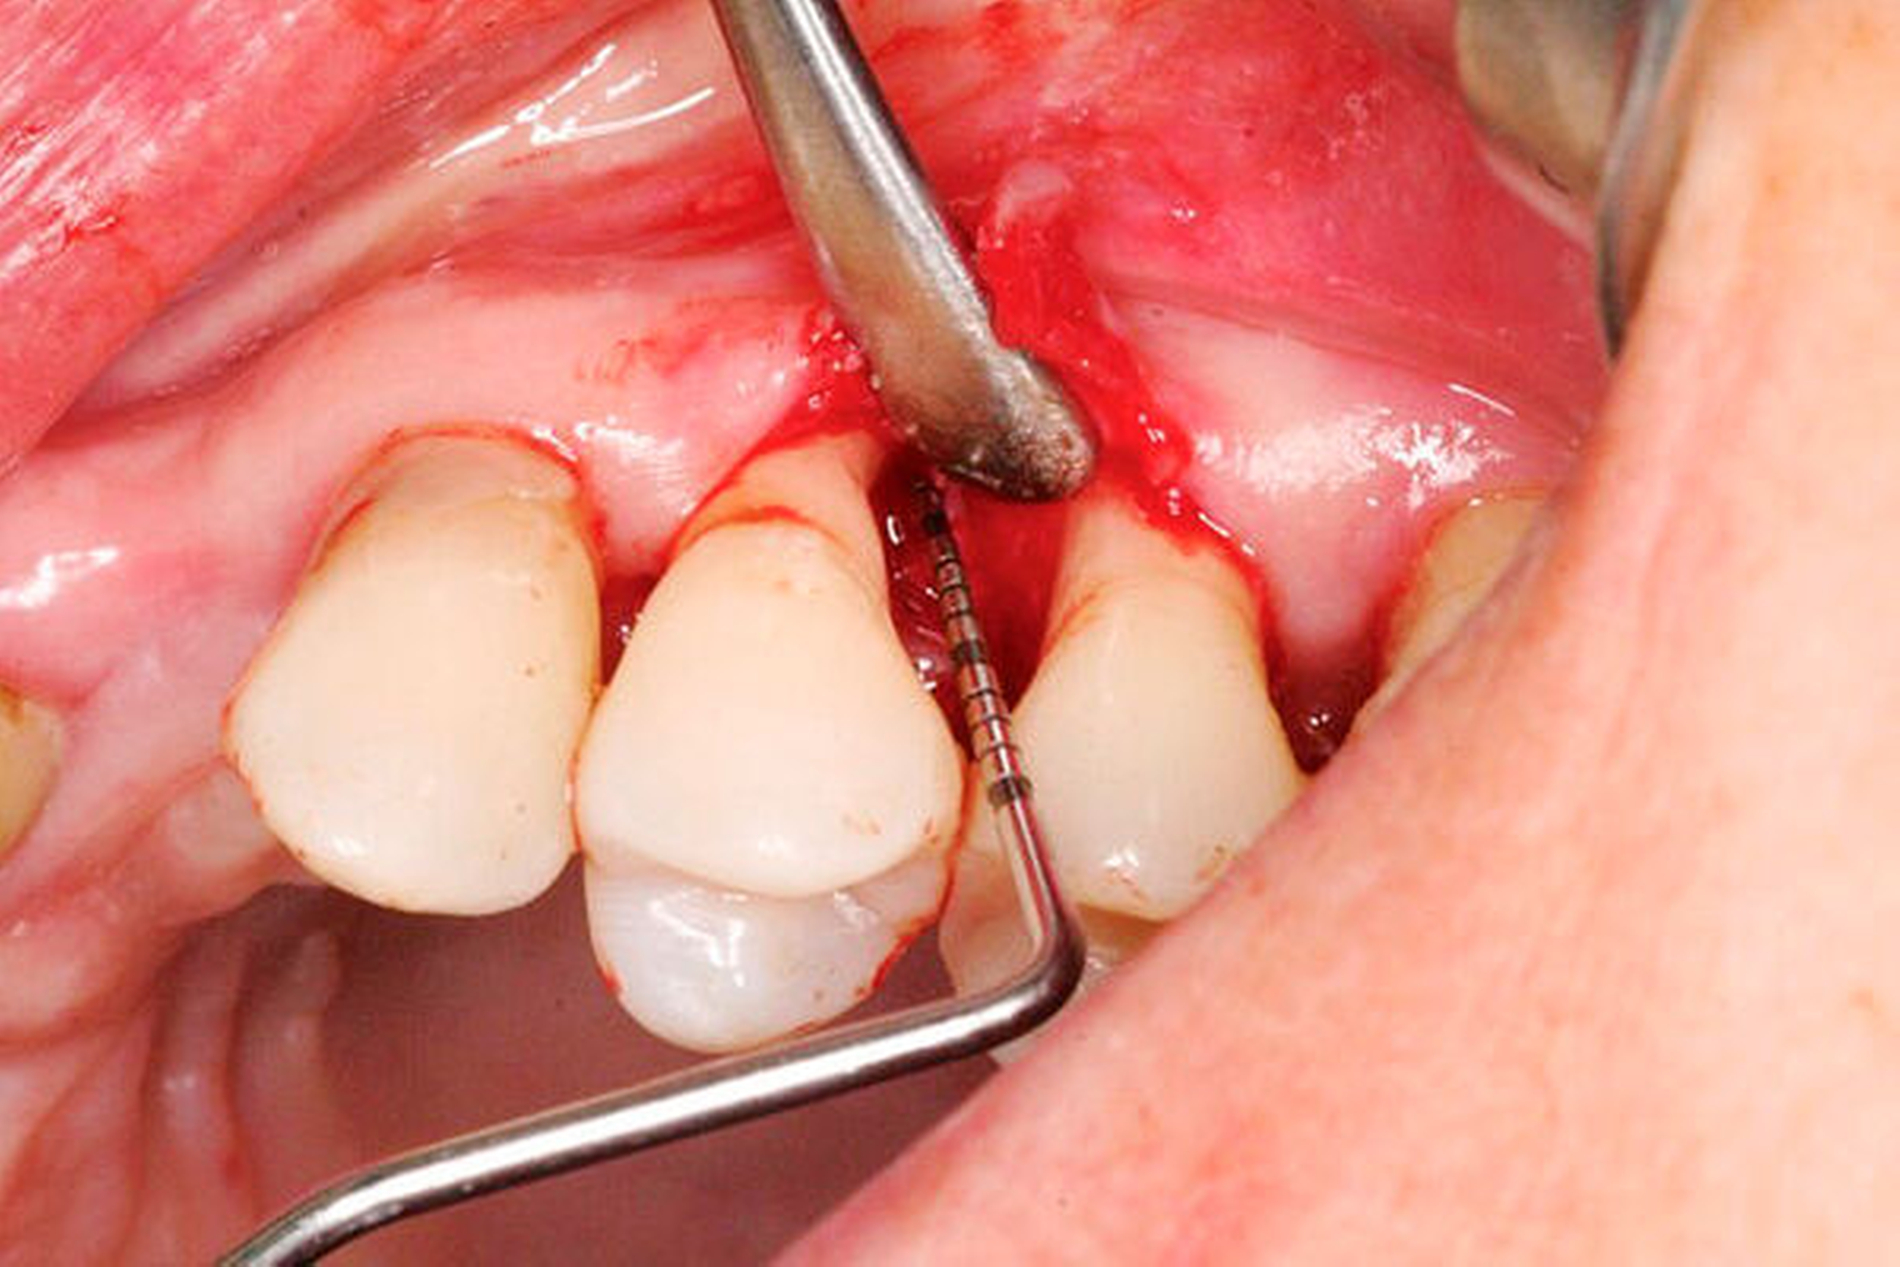

Lappenoperationen haben im Wesentlichen die Aufgabe, die Sicht in ein Gebiet zu ermöglichen, das bei der bisherigen Therapie nicht eingesehen werden konnte. Dies ist von besonderer Bedeutung für Furkationsbefälle höheren Grades und Knochentaschen, vorwiegend in Verbindung mit tiefen Resttaschen (TST ≥ 6 mm). Andererseits soll die Lappenoperation zur weiteren Reduzierung der Sondierungstiefe beitragen, um ein längerfristig stabiles Therapieergebnis zu erzielen, das mit Taschentiefen bis 4 mm ohne Bluten auf Sondieren beschrieben ist [Serino et al., 2001]. Vor der Intervention ist die Indikation jedoch kritisch zu prüfen, denn je nach Methode kann die Lappenbildung in seltenen Fällen unerwünschte Nachwirkungen wie Blutungen, Nervschädigungen oder Entzündungen haben. Für ästhetisch sensible Bereiche ist das Auftreten von Rezessionen zu bedenken und mit dem Patienten abzustimmen. Auch auf den Eingriff folgende Hyperästhesien können nicht vollständig ausgeschlossen werden.

Bei moderaten Resttaschen (TST 4 bis 5 mm) nach der ersten und zweiten Therapiestufe führen Lappenoperationen zwar kurzzeitig für bis zu zwölf Monate zu einer stärkeren Verringerung der Sondierungstiefe als die subgingivale Instrumentierung (+0,34 mm, +29,6 Prozent in vier in die Auswertung einbezogenen Untersuchungen), bei sieben längerfristigen Studien (> 12 Monate) ist dieser Vorteil geringer und wird mit 9,49 Prozent höherer Taschentiefenreduktion angegeben [Sanz-Sanchez et al., 2020]. Der Anteil flacher Taschen nach der Therapie war bei Anwendung eines Zugangslappens 11,6 Prozent höher. In Bezug auf ein verbessertes klinisches Attachmentlevel (clinical attachment level: CAL) wurden keine statistisch signifikanten Unterschiede zwischen den Interventionen bei initial tiefen Taschen beobachtet. Der CAL-Gewinn war jedoch in der Gruppe der subgingivalen Instrumentierung signifikant größer bei Taschen, die initial eine moderate Tiefe hatten. Bei Taschen mit einer TST ≤ 4 mm waren durch die Zugangslappenbildung signifikante Attachmentverluste zu verzeichnen. Die Lappenoperation bleibt evidenzbasiert höheren Sondierungstiefen (TST ≥ 6 mm) vorbehalten, sollte dort jedoch erfolgen.